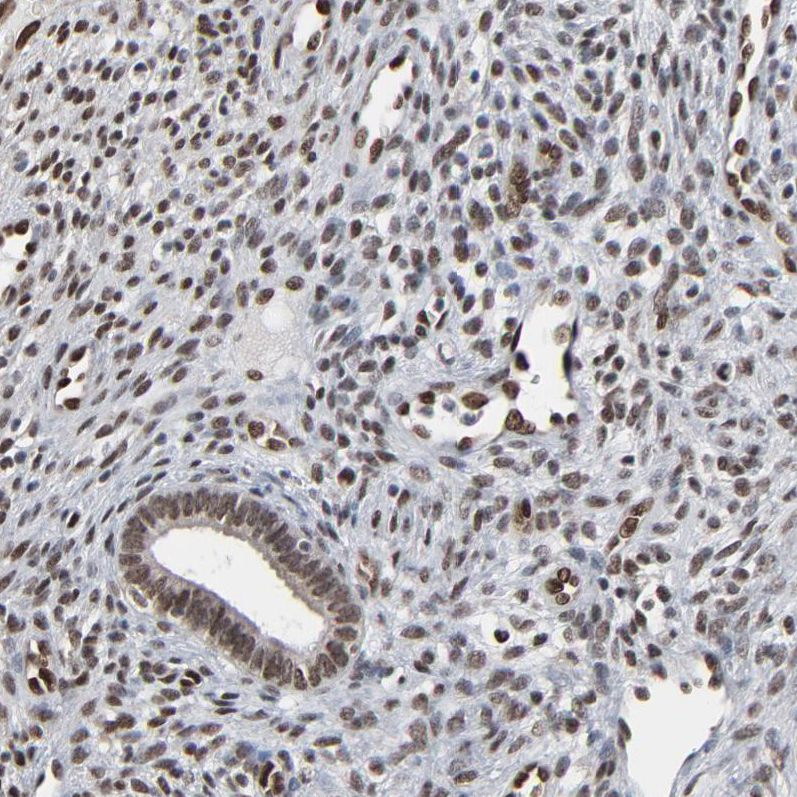

Immunohistochemical staining of human endometrium shows moderate nuclear positivity in glandular and stromal cells.